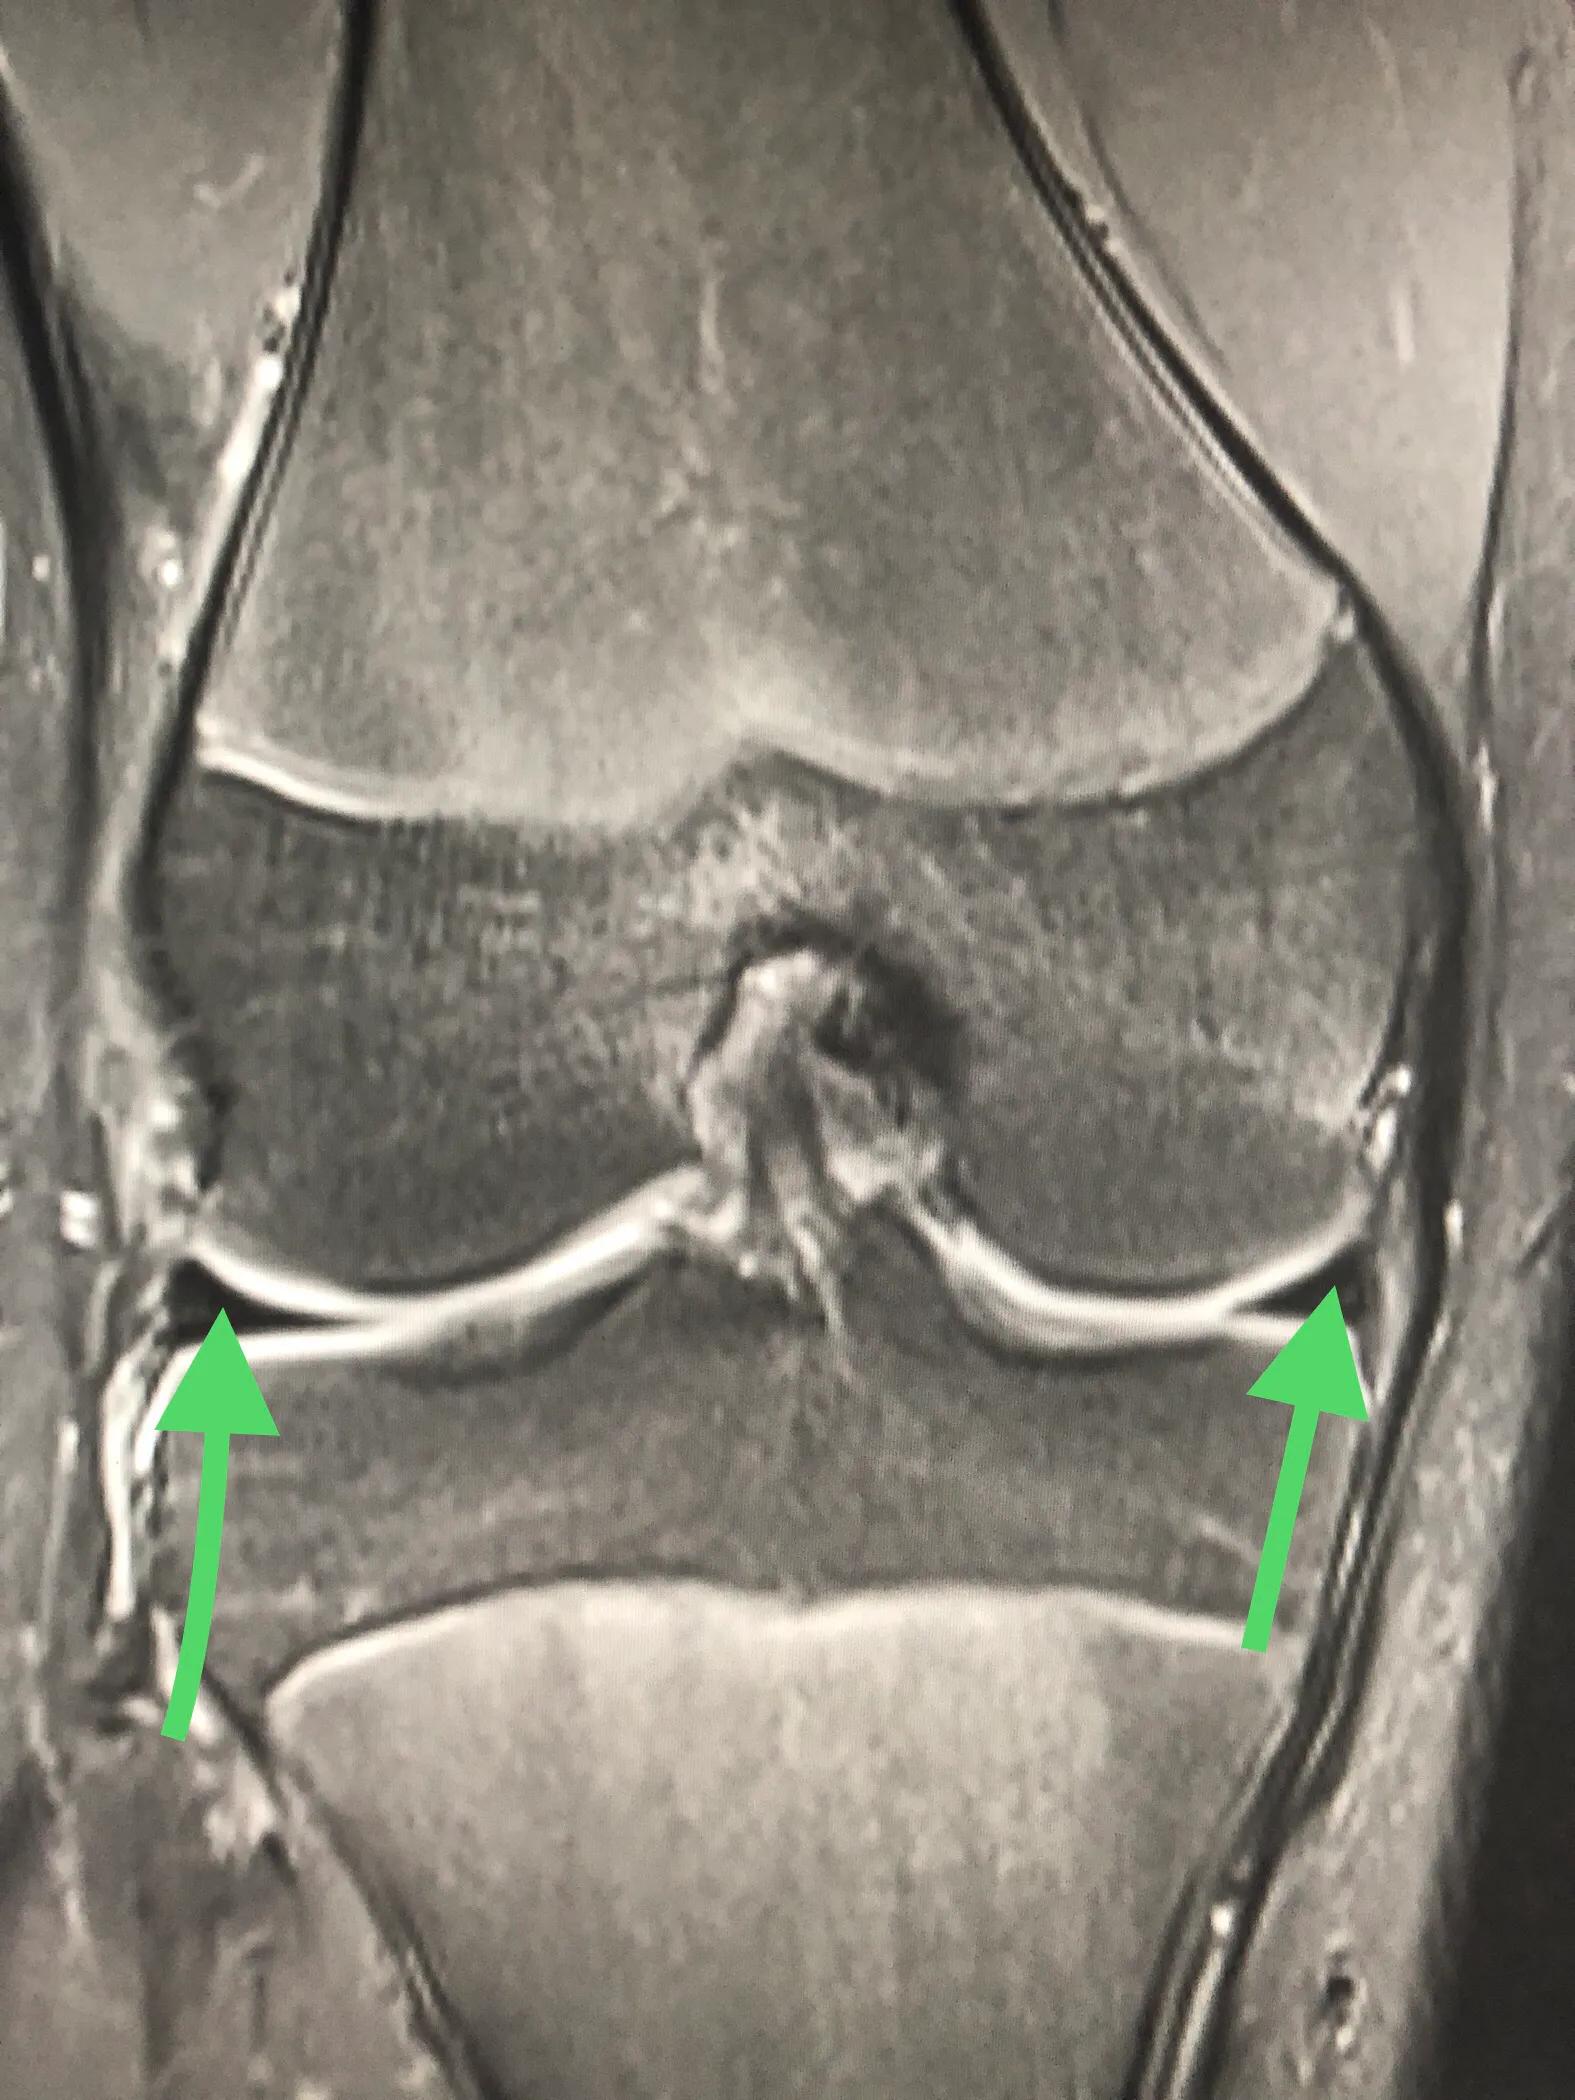

外侧盘状半月板的桶柄样撕裂:两枚绿箭头之间的条状物便是盘状半月板,已经撕裂,需要手术。

换个方向看肥厚的盘状半月板,绿箭头之间的那块便是,已经撕裂,需要手术。